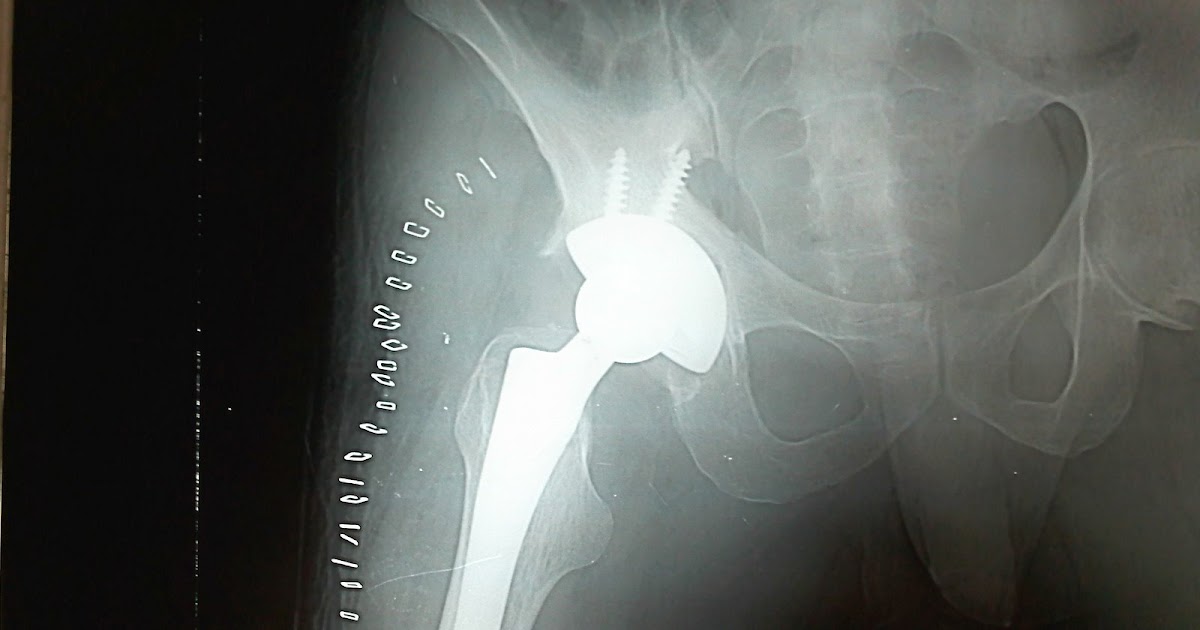

From clinicalimages.blogspot.com

Clinical images Total Hip Replacement Gun Stock Deformity Hip The aim of the study. pistol grip deformity describes the abnormal shape of the hip joint. early hip joint degeneration is a common clinical presentation and preexisting abnormal joint morphology is a risk factor for its. Stulberg and associates back in. a decreased head/neck offset has been recognized on ap pelvic views and labeled as pistol grip. Gun Stock Deformity Hip.

Clinical images Total Hip Replacement Gun Stock Deformity Hip Stulberg and associates back in. early hip joint degeneration is a common clinical presentation and preexisting abnormal joint morphology is a risk factor for its. a decreased head/neck offset has been recognized on ap pelvic views and labeled as pistol grip deformity. The aim of the study. pistol grip deformity describes the abnormal shape of the hip. Gun Stock Deformity Hip.